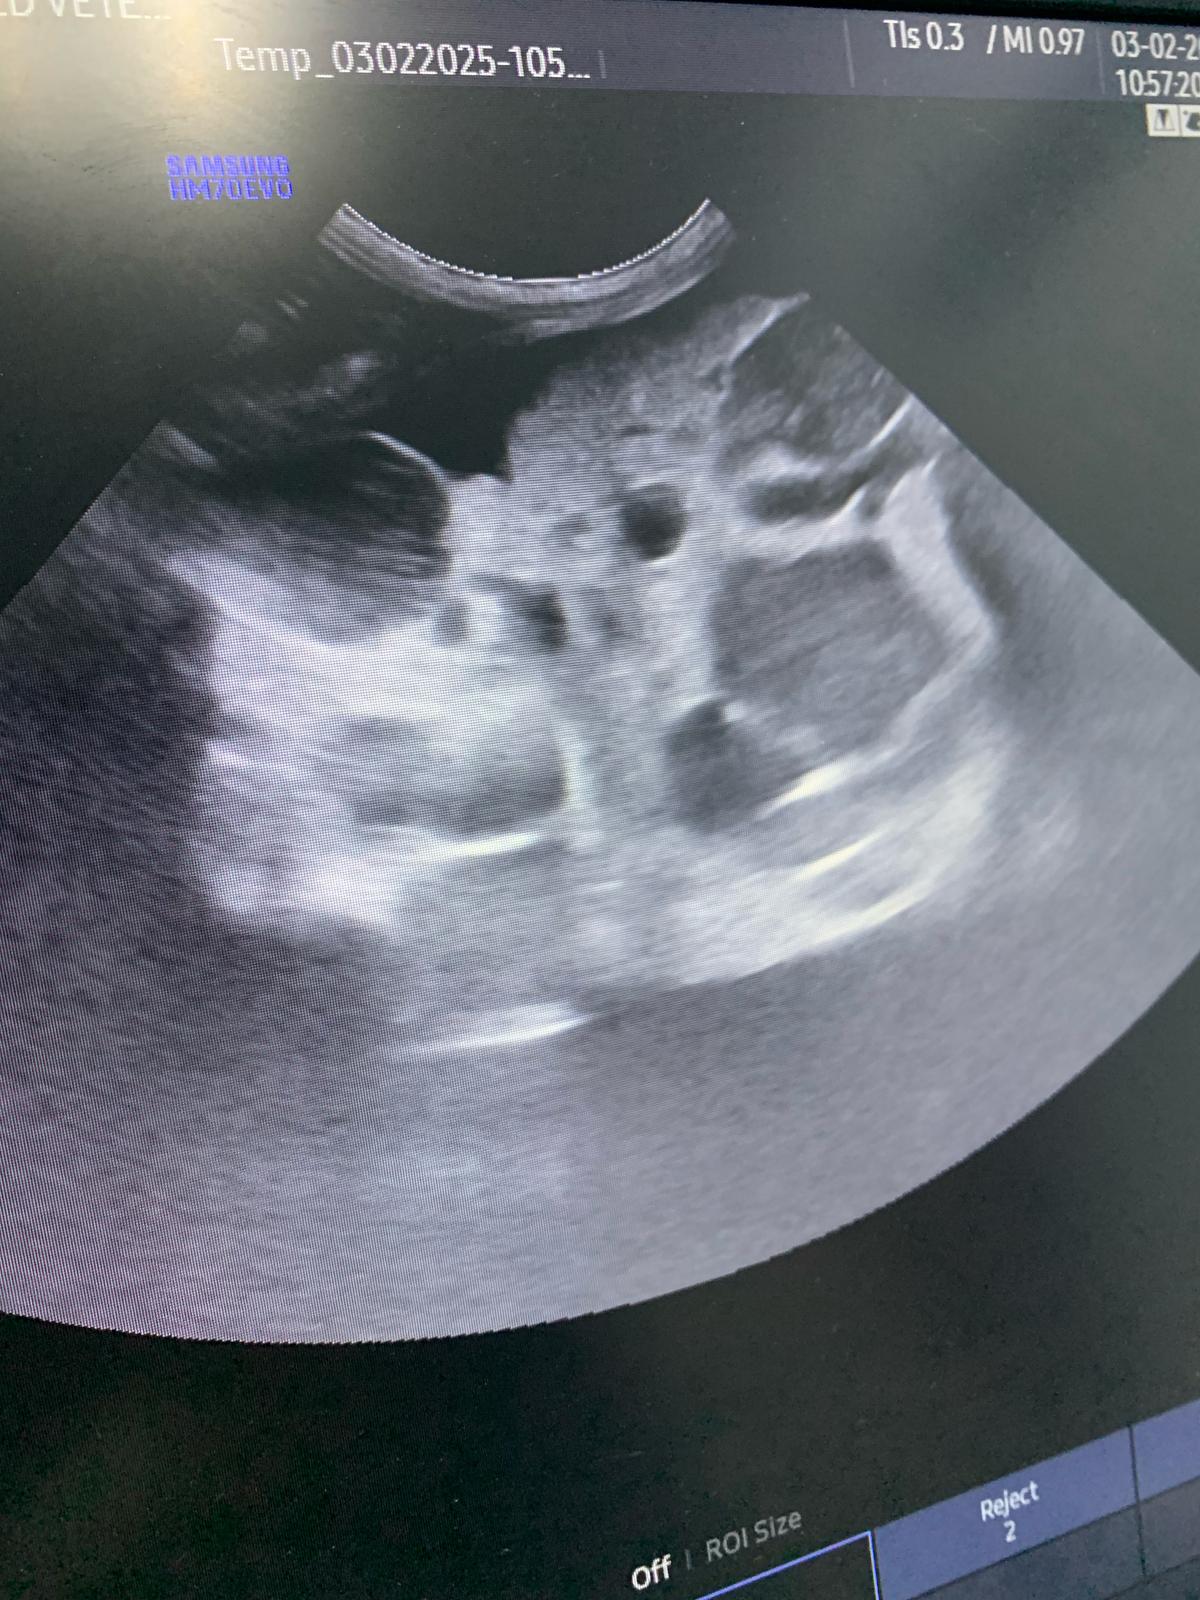

Dr d says she show dr ym aw u/s pic and she Duno what it is, meant be the shots r bad or what. They will do it at their end.

10.33am: dr d show me an u/s says don don kidney r the worst she had ever see, full of cysts for both kidneys. She remember Raichu so this family has a bad gene of cysts issue pass down. Don fluid r ard the kidneys, not the same as norm cats who had fluid ard the intestine, she said dr ym says it’s the same as last time, so she is confident of tapping, will do it away fr the kidneys. But the tapping won’t stop the cyst from leaking again. (Dr d mention more them twice that cysts r painful) noted that the tapping is more benefial to don don, only damage is my pocket) and the coming back is next time biz (maybe monthly tapping see how first).

11.38am: seen dr nally. She did hear mur mur. 3.48kg – gain 220g in 3 days, gain fluid. Taken a quick u/s scan, his cysts are all surrounded by a big ball of fluid (scary as in not sure is it the kidney itself, if yes, means the kidney super swell) or ???! N yet there are still some (little) free fluid outside the ball. For both side. Rejected the tapping. Too dangerous, might just burst the kidney/ ball.

Dr told me to go in to see her scan – both kidneys irregular in shape, like got holes like that (pic la, but he got multiple cysts on his kidneys) liver ok.